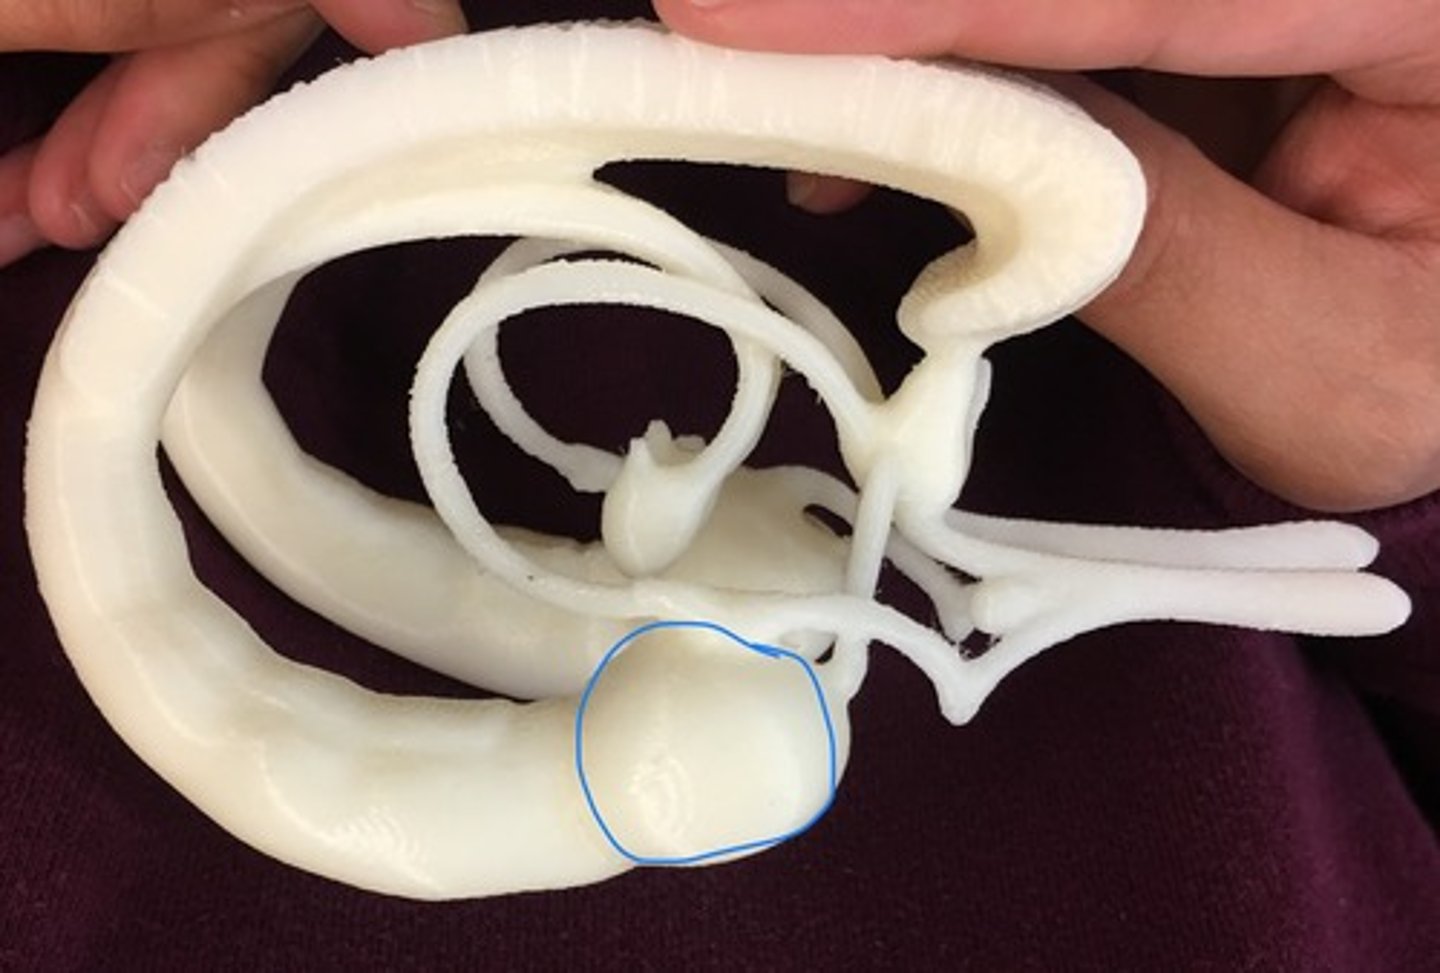

hippocampus

Mammillary body

Pituitary gland

choroid plexus

lateral ventricles

cerebral aqueduct

third ventricle

fourth ventricle

arbor vitae

Amygdala